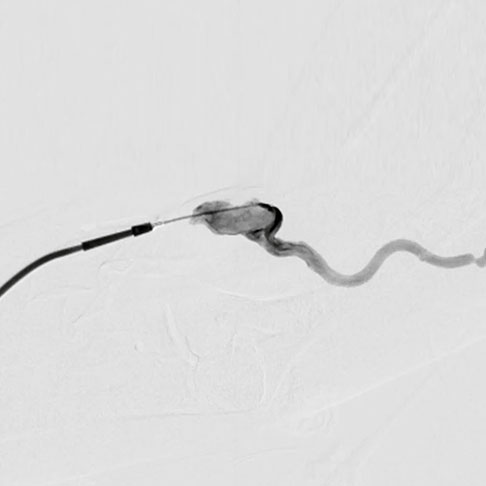

피부에 작은 구멍을 내고 그 내부로 카테터나 시술 기구를 삽입하여 다양한 질환을 진단하고 치료하는 의학분야로

주로 혈관조영기 같은 영상장비를 이용해 신체 내부 구조를 관찰하면서 시술을 진행합니다.

대학병원에서 수년간 쌓아온 풍부한 시술경험과

최신 혈관조영장비를 이용하여 정확한 진단과

안전하고 효과적으로 치료를 시행하고 있습니다.